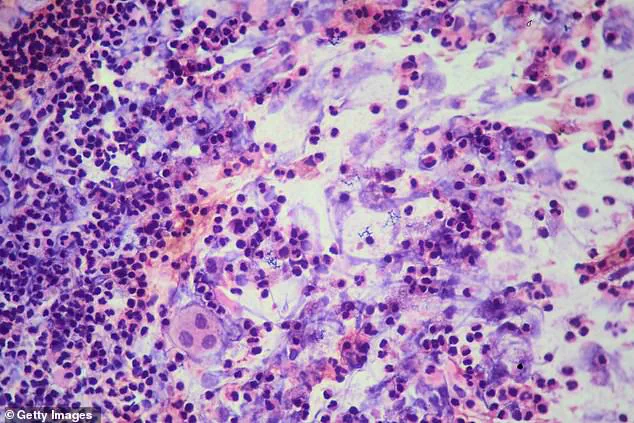

Tuberculosis, a bacterial infection primarily spread through airborne droplets from coughs and sneezes, often presents initially with symptoms resembling a cold or flu.

Untreated TB can lead to severe complications, including lung damage and systemic failure, underscoring the importance of early detection and intervention.